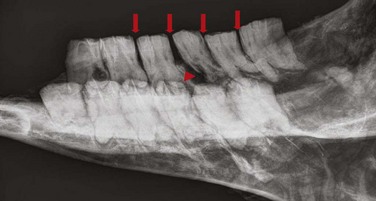

image image image

Fig. 13.36 Polydontia. Supernumerary maxillary cheek teeth (Triadan12s) are the most common supernumerary cheek teeth in horses. The 12 is usually markedly overgrown as in (A) but may be unerupted as in (B) if there is inadequate space (overcrowding). Note the abnormal shape of the apical area of the 112. (C) An example of overgrown bilateral supernumerary mandibular 12s.